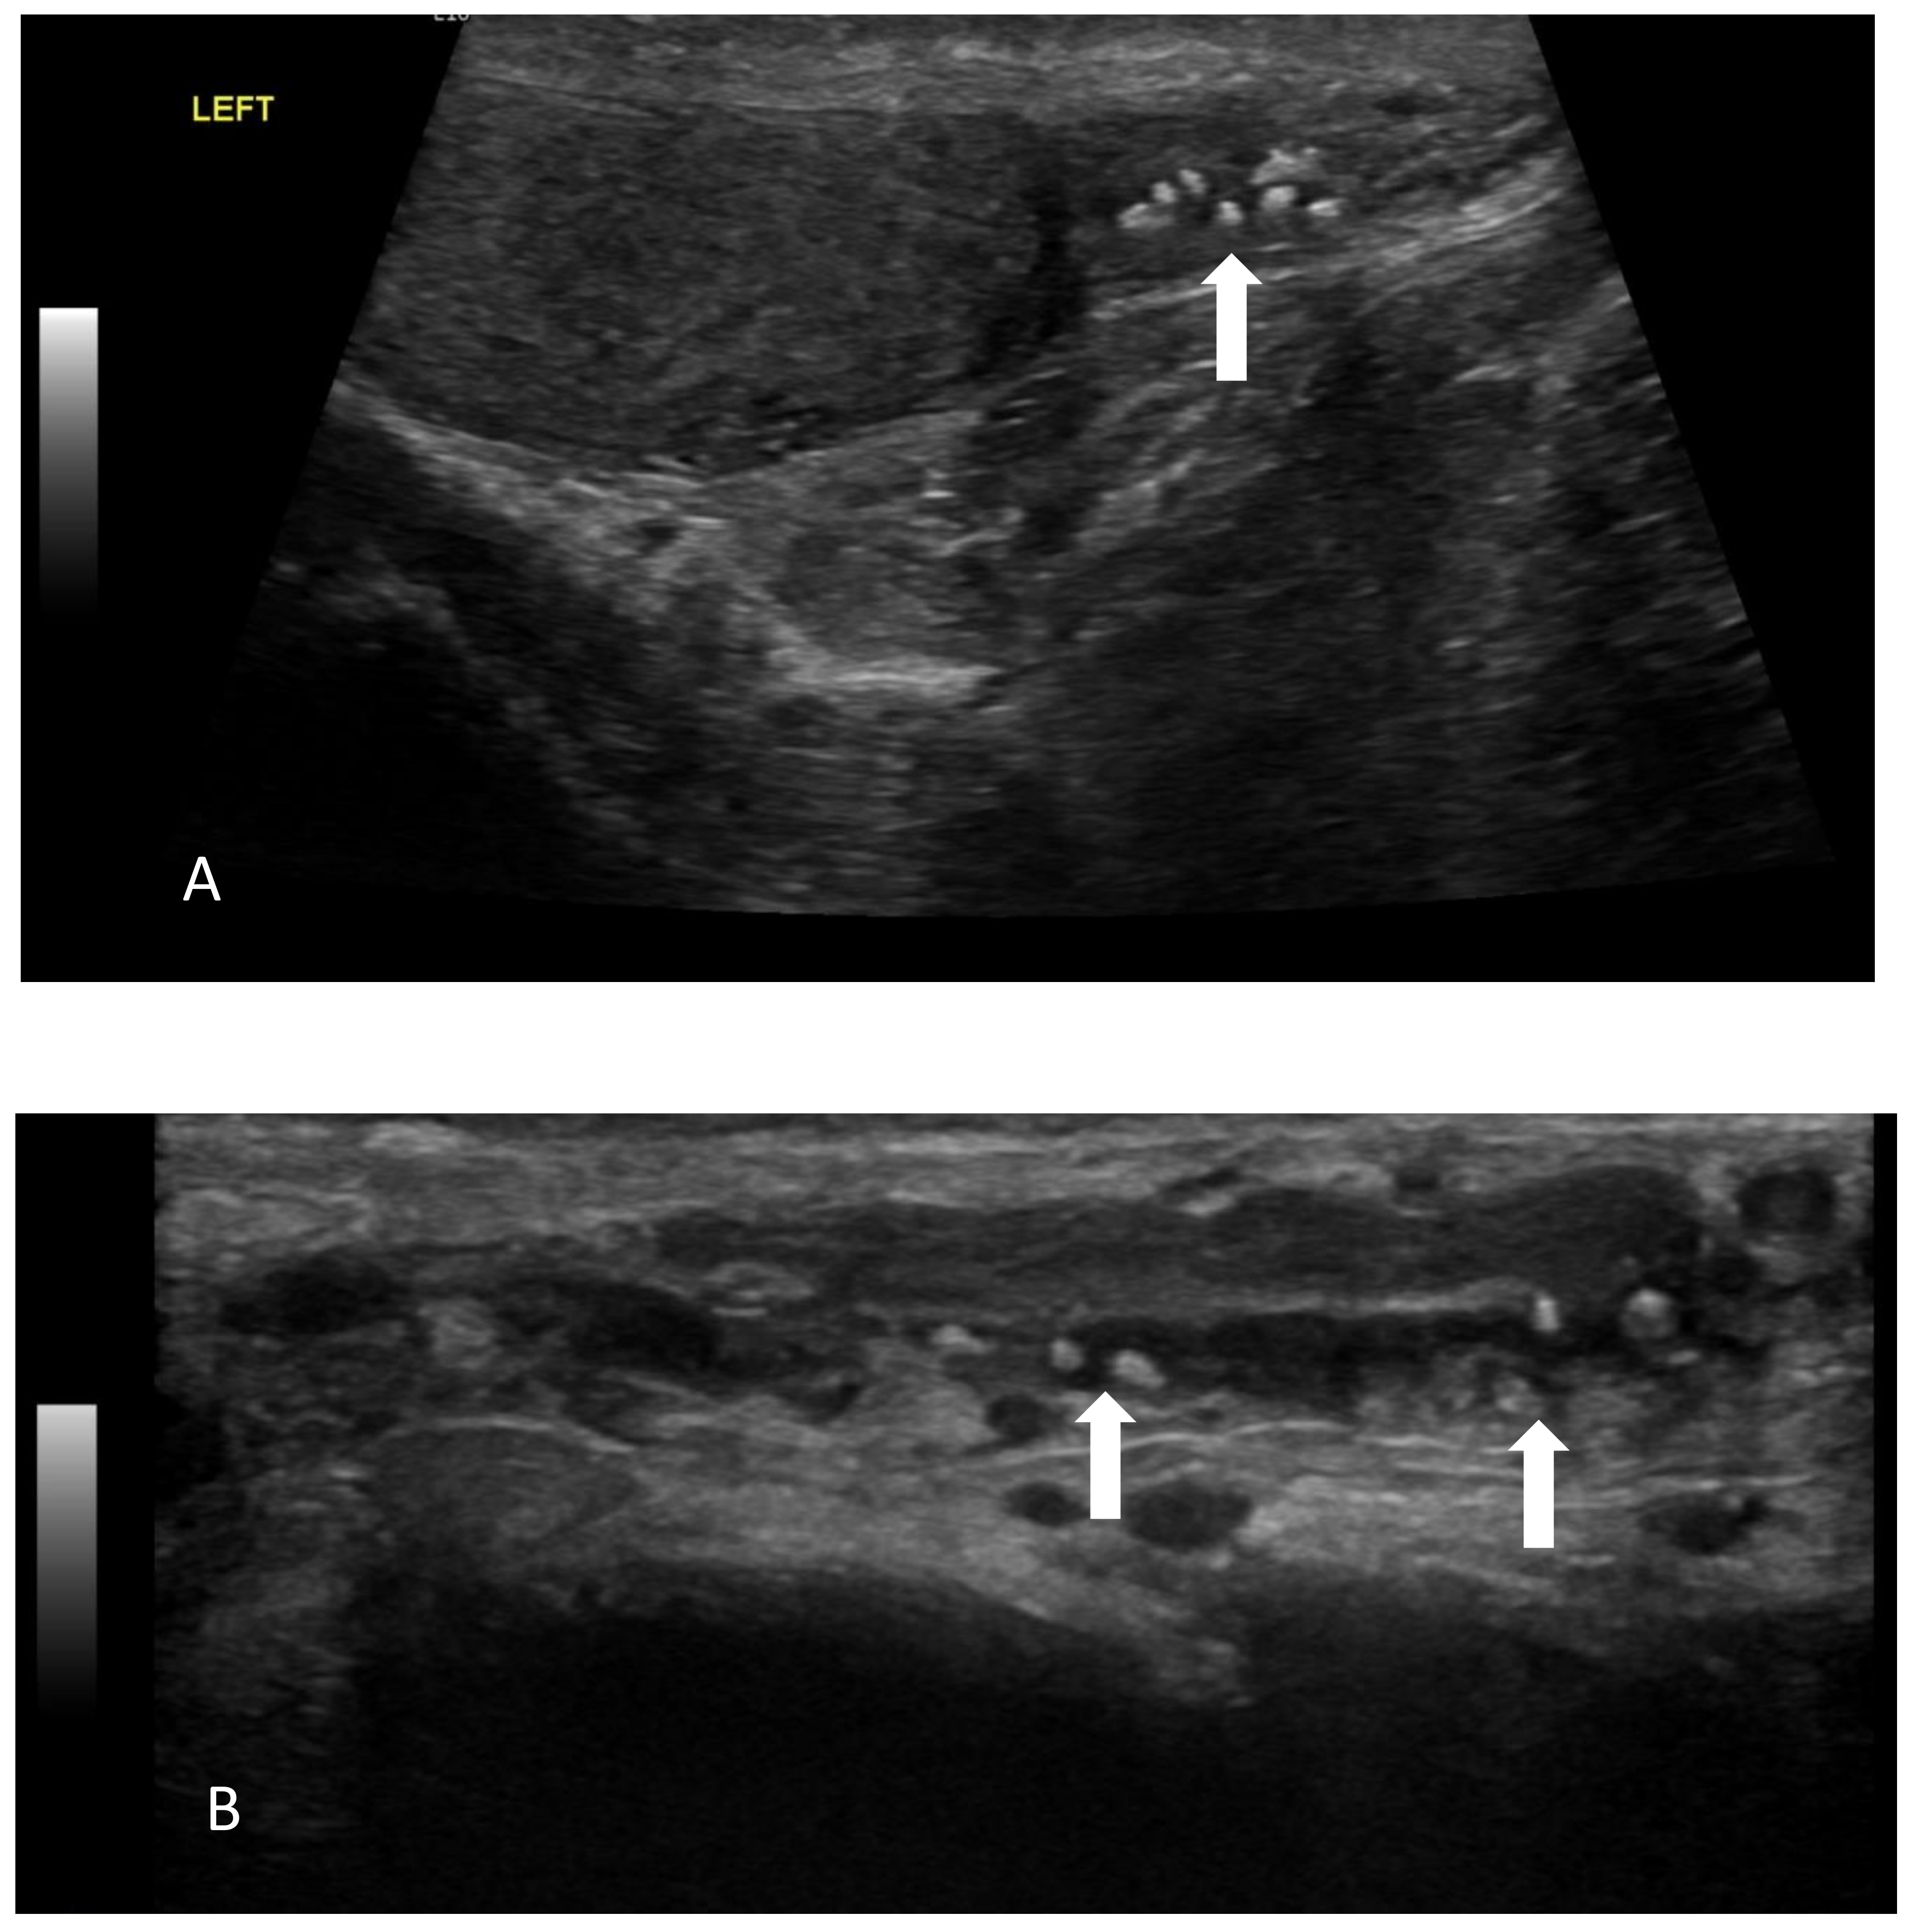

- A case of a patient with AIP type 1 and other organ involvement (bile ducts, testicles, nasal polyps, and lungs) is described.